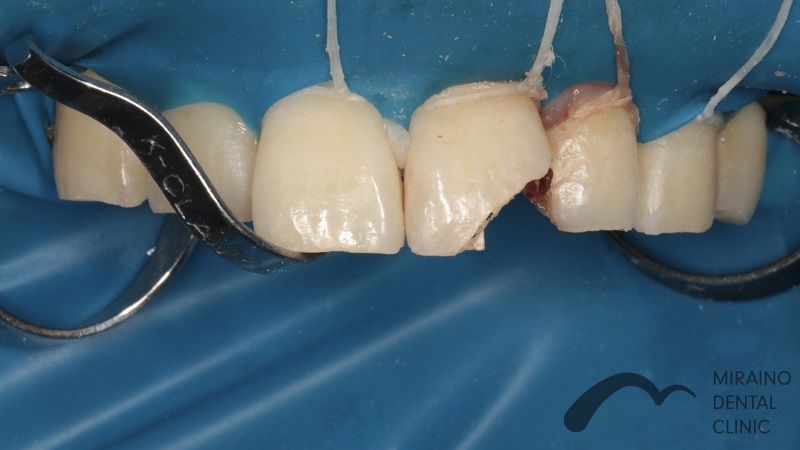

外傷の症例

Case1

| 施術名 | 外傷・神経の保存 |

| 治療の概要 | 仕事中の事故により歯が欠けて来院されました。 神経まで露出しており従来の治療基準では神経を取らねばなりませんが、 神経を残す新しい材料MTAにより神経を保存する治療を行いました。 3ヶ月経過観察後、歯の神経の感染壊死の症状が見られなかったため、 神経を残しながら汚れのつきにくい素材で被せ物を装着しました。 |

クリックして詳細を表示

| 施術の内容 | 歯の神経が見えてしまった際に抗菌作用の材料MTAで神経を温存する治療です。 ラバーダムを用いて唾液による感染のリスクを排除し無菌的な治療を行います。 |

| 1歯あたりの治療費 | 35,000円 |

| 考えられるリスク、副作用 | 治療後、痛みや違和感、出血、腫れ、麻痺などが出る事があります。 |

| 考えられるリスク、副作用[麻酔] | 麻酔を行う場合、腫れやむくみを生じる事があります。 |

| 補綴 | 仮歯の期間中は仮歯の部分で噛むと破損する場合があります。 |

| 根治 | 治療に際して、根の治療が必要になる場合があります。 被せ物をかぶせた後に根の病気が再発した場合、被せ物を外さなければならない事があります。 (外した被せ物の再利用は多くの場合、出来ません) |

| 施術名 | セラミック |

| 施術の内容 | 歯の表面を歯の表面を削って強度の高いジルコニアクラウンを被せて歯を補強します。 |

| 1歯あたりの治療費 | 80,000~150,000円 |

| 考えられるリスク、副作用 | 治療後、痛みや違和感、出血、腫れ、麻痺などが出る事があります。 |

| 考えられるリスク、副作用[麻酔] | 麻酔を行う場合、腫れやむくみを生じる事があります。 |

| 考えられるリスク、副作用[咬合] | また、歯並びが変わる事により違和感を生じる事があります。 神経の治療や抜歯が必要な場合があります。 |

| 補綴 | 強い衝撃を与えると、被せ物が欠けたり割れたり、外れたりする事があります。 仮歯の期間中は仮歯の部分で噛むと破損する場合があります。 |

| 根治 | 治療に際して、根の治療が必要になる場合があります。 根の治療を行った場合、腫脹や出血、痛みなどを生じる事があります。 被せ物をかぶせた後に根の病気が再発した場合、被せ物を外さなければならない事があります。 (外した被せ物の再利用は多くの場合、出来ません) |

| 全て | 必ずしもご希望通りの見た目にならない事があります。 |